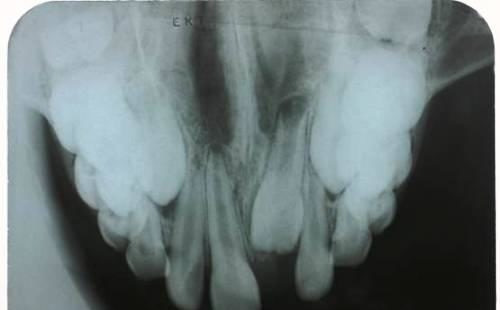

Rx Oclusal

Sirven para observar:

- Raíces retenidas de dientes extraídos.

- Dientes supernumerarios (extra), no erupcionados o impactados.

- Cuerpos extraños en maxilar o mandíbula.

- Cálculos salivales en los conductos de la glándula mandibular.

- Ayudar en el examen de pacientes que no pueden abrir su boca más que unos milímetros.